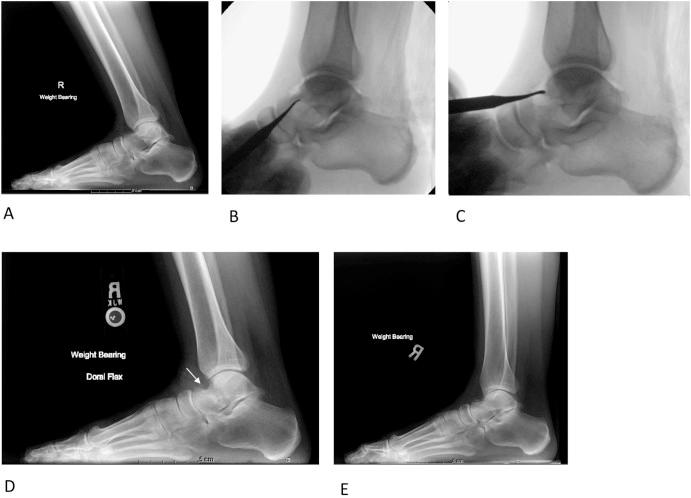

距骨不全骨折并发踝关节唇切除术

Talar insufficiency fracture complicating ankle cheilectomy.

Ankle cheilectomy as surgical treatment for anterior ankle impingement has high rates of procedural success and low rates of complications when performed before the onset of significant osteoarthritis. We present 3 patients who developed insufficiency fractures of the talar neck following cheilectomy for anterior ankle impingement. Due to the high risk of avascular necrosis associated with displaced talar neck fractures, the recognition of talar insufficiency fractures by the radiologist can aid in the timely diagnosis and initiation of intervention. Because radiographic findings of stress fractures often require weeks to manifest, maintaining a high index of suspicion in the postcheilectomy setting allows the radiologist to suggest appropriate further imaging when appropriate.

摘要

踝关节切骨术作为治疗前踝撞击症的手术方法,在严重骨关节炎发作前进行时,手术成功率高且并发症发生率低。我们报告3例因前踝撞击症行踝关节切骨术后发生距骨颈不全骨折的患者。由于移位的距骨颈骨折与缺血性坏死风险高相关,放射科医生识别距骨不全骨折有助于及时诊断并启动干预。因为应力性骨折的影像学表现通常需要数周才能显现,所以在踝关节切骨术后保持高度怀疑指数可使放射科医生在适当的时候建议进行适当的进一步影像学检查。